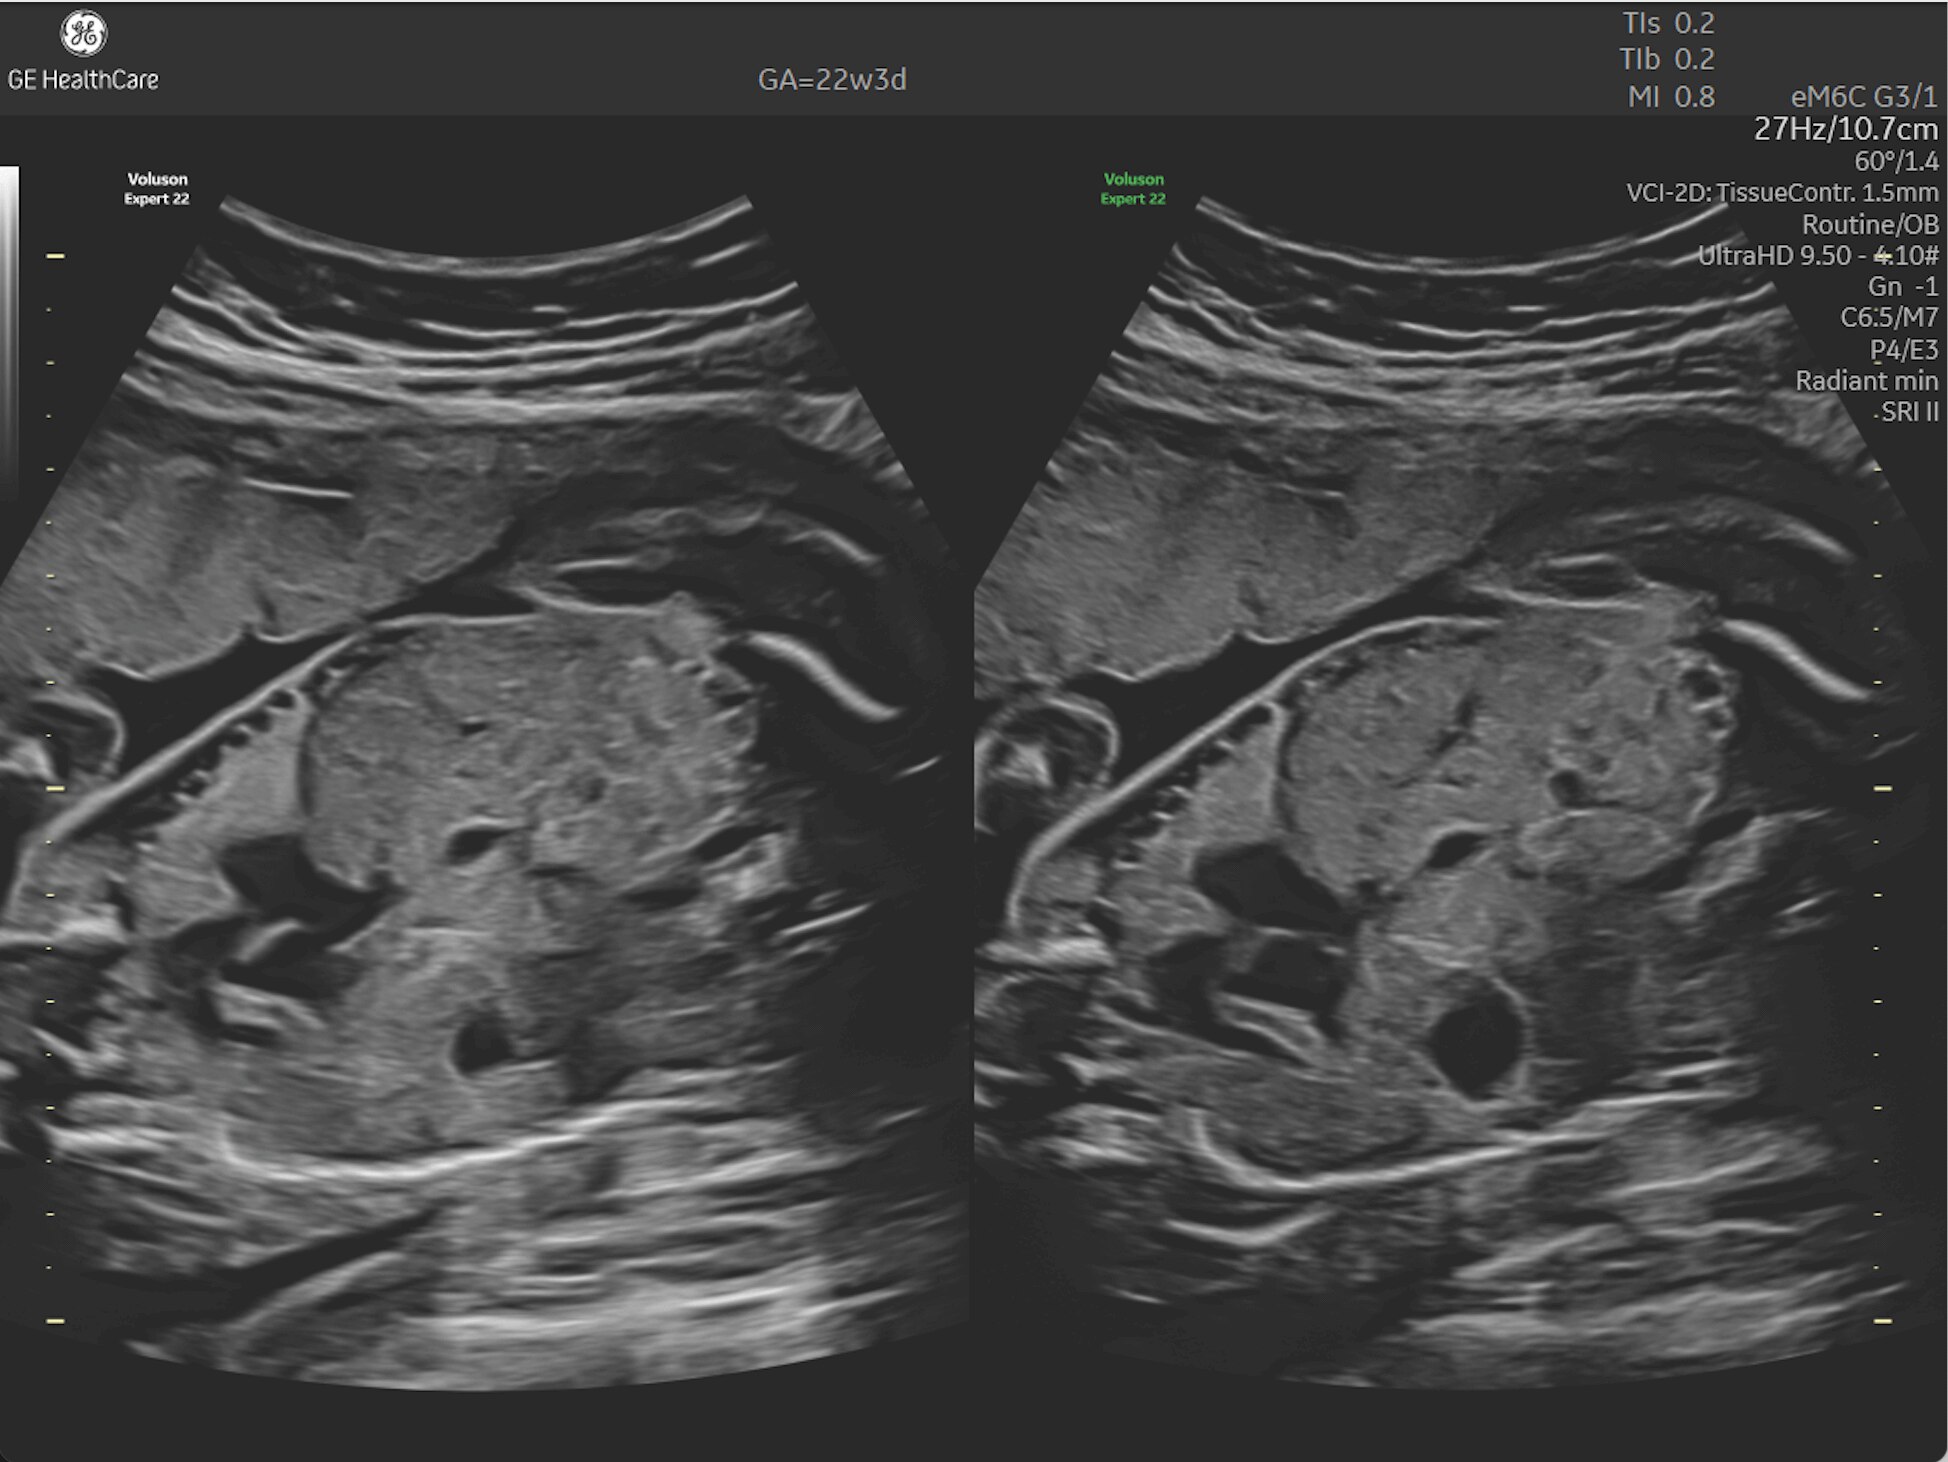

First Trimester Exams

Perform detailed exams with high-resolution for early insights to fetal health